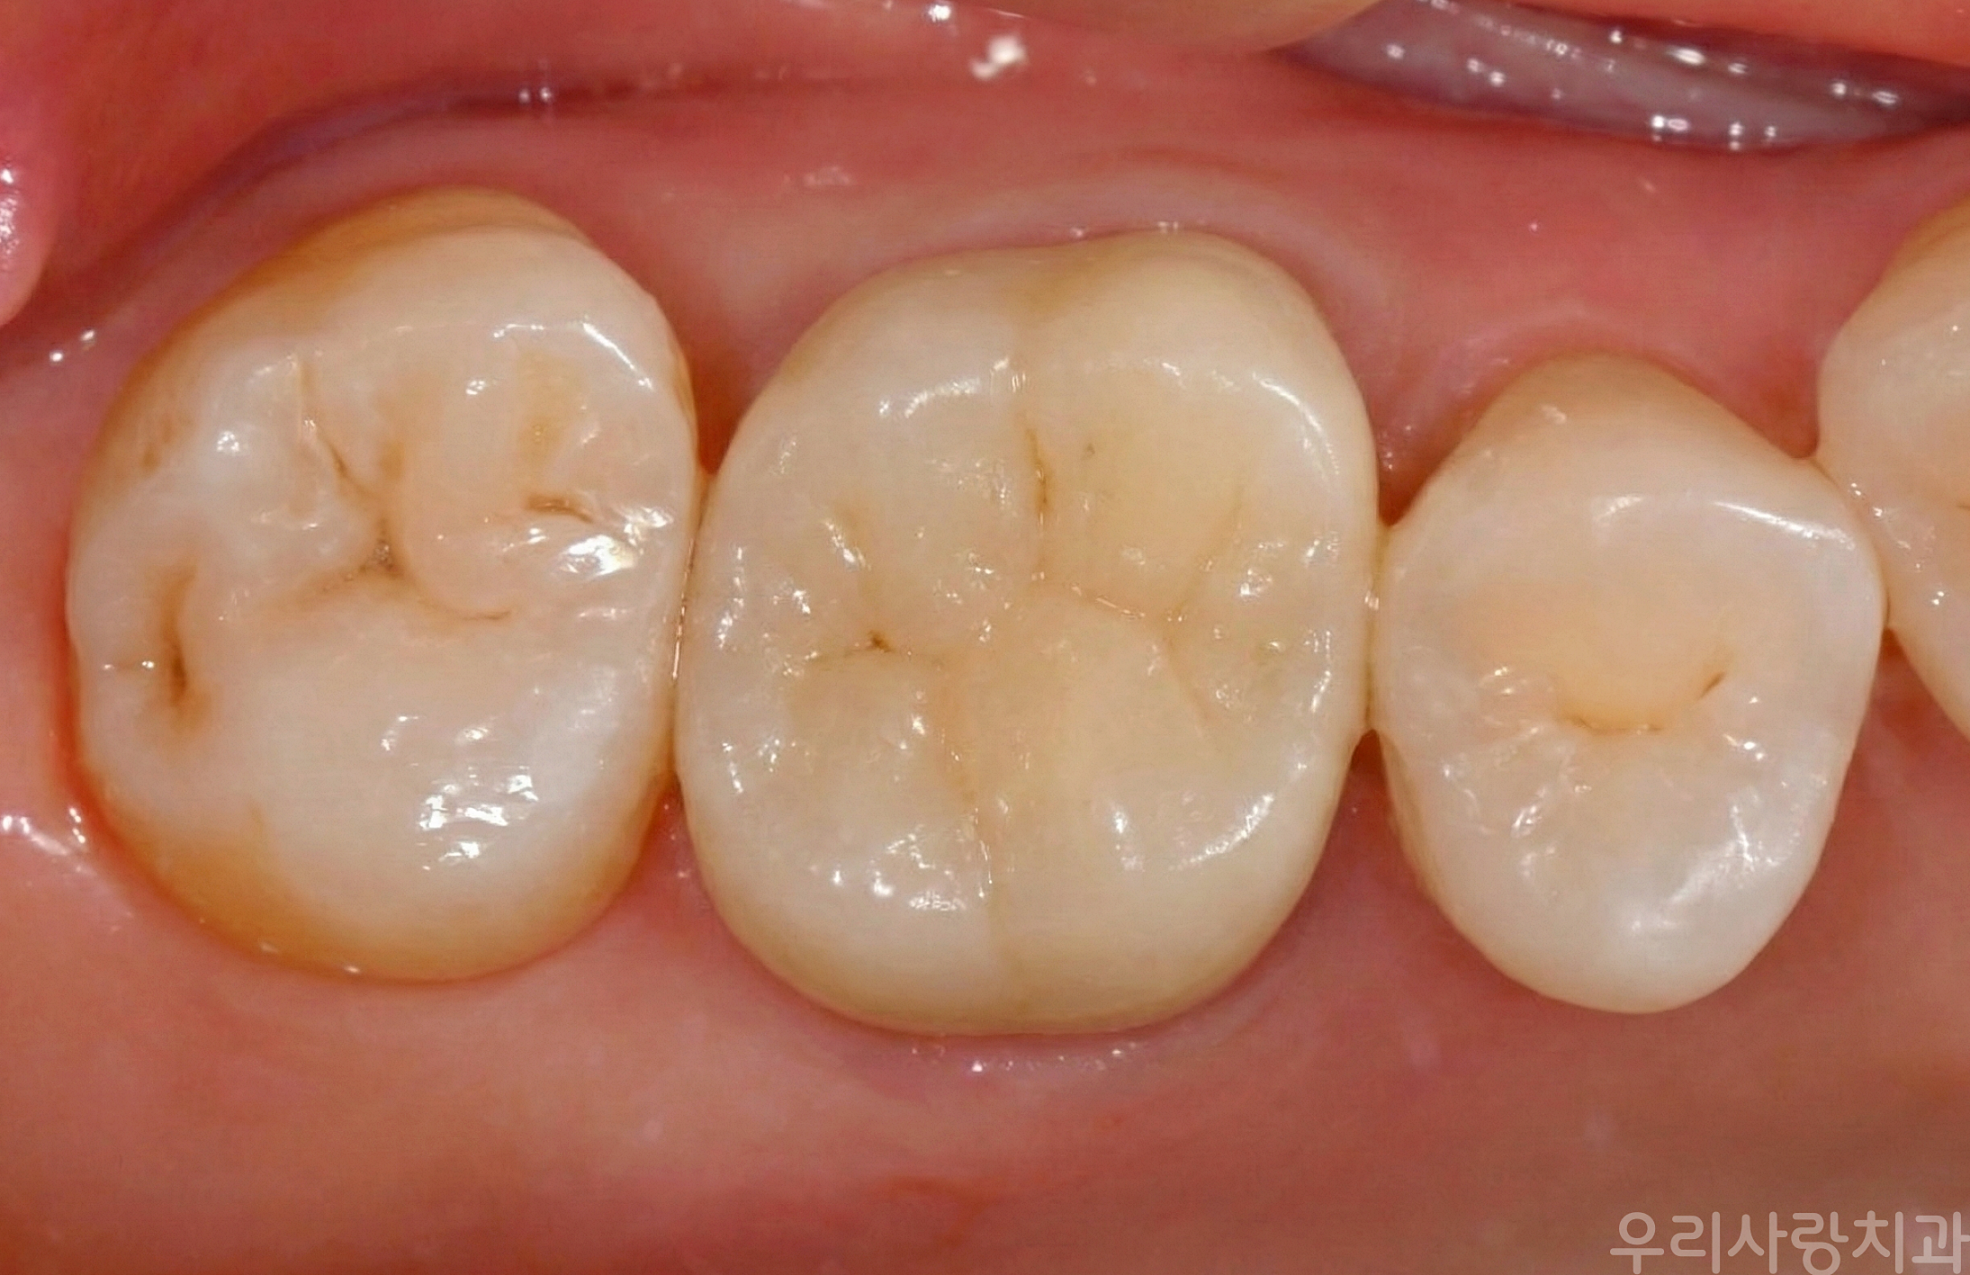

▲ 지르코니아 크라운 장착 후 모습: 자연 치아와 구분이 어려울 정도로 자연스럽고 틈 없이 매끈하게 연결되었습니다.